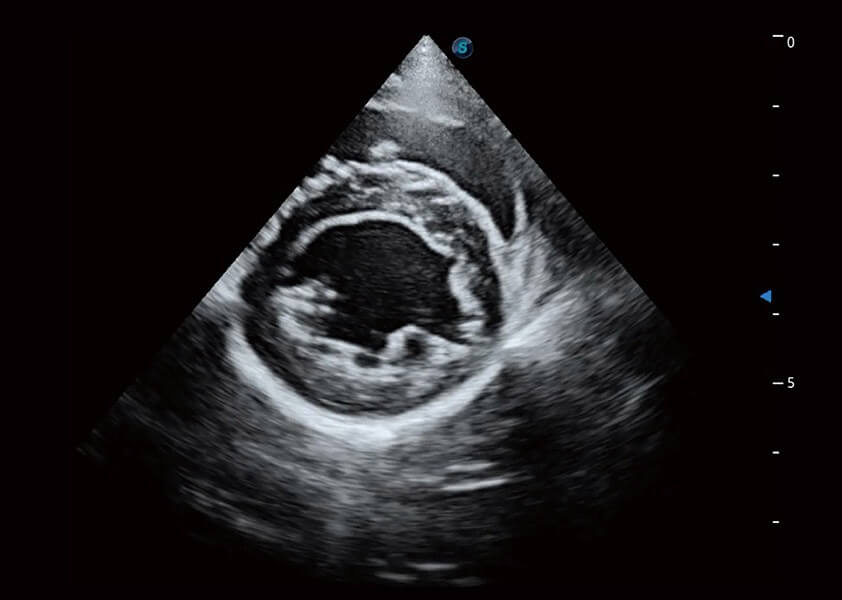

ProPet 60 作为一款高端台式动物超声设备,为动物医生的日常诊断提供了一系列贴合动物临床需求、解决临床实际问题的高级成像功能。凭借全系列高清探头,满足医生对腹部、心脏、生殖、浅表、肌骨等成像的所有需求,切实帮助您提升检查效率,提高诊断信心。

兽用彩色多普勒超声诊断系统

动物是人类最亲密的朋友和最值得信赖的伙伴。玖鼎集团也一直致力于探索动物专用的超声影像解决方案。 全新推出的ProPet系列,是玖鼎集团在动物超声影像智能化、专业化、精准化的一次跨越式革新。动物不能用言语来表述自己的不适,通过超声影像,ProPet系列搭建了动物医生与不同物种沟通的“桥梁”,为动物医生注入了“治愈之力”。